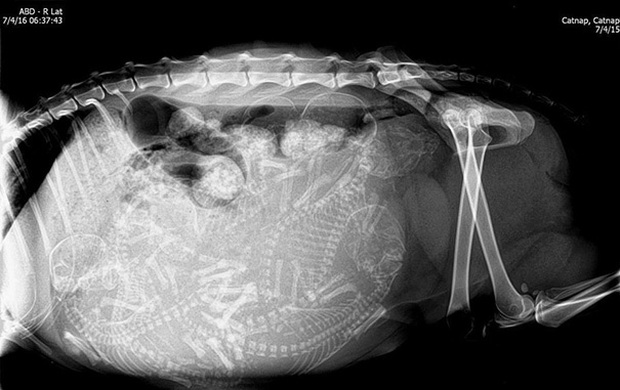

Một bà mẹ mèo đang mang thai. Thời gian thai kỳ của mèo khoảng 56 - 71 ngày, trung bình kéo dài khoảng 67 ngày và chúng có thể "sản xuất" 3 - 4 lứa mỗi năm.

Cận cảnh hình chụp X-quang một cô mèo đang mang thai và loạt ảnh động vật mang bầu khiến người xem rùng mình nhưng rồi thấy đẹp khó tả - Ảnh 6.